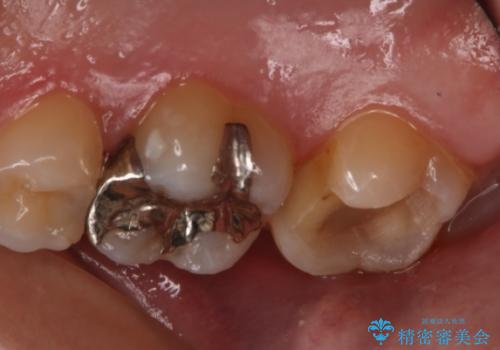

- 右上大臼歯の再治療を希望され来院された患者様です。

切削量と形状を考慮し、インレーでの治療を計画しました。

患者様がゴールドを希望されたのでゴールドインレーを選択しました。